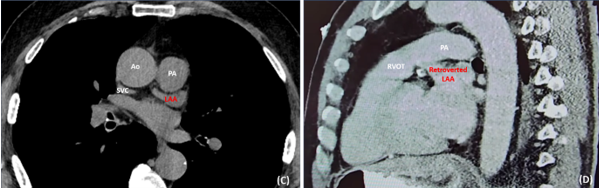

Retroverted LAA is not a widely recognized anatomical variant and its incidence has not been reported. Unlike an anteverted LAA, its tip is not in its usual location (lateral to the PA) and is, therefore, not readily visible endoscopically (Figures 1A, B). This is because it runs in the transverse sinus, which is posterior to the right ventricular outflow tract, PA, and aorta (Figures 1C, D). The base or neck of the LAA remains unchanged.

Cardiac computed tomography with contrast enhancement is very reliable in identifying a retroverted LAA preoperatively (Figures 1C, D). Magnetic resonance imaging is as useful, especially in patients with contraindication to contrast. Transesophageal echocardiography, which is routinely performed to assess for LAA thrombus preoperatively, can help identify a retroverted appendage.

Figure 1A, B. A and B are endoscopic views of the mediastinum: A illustrates the close relationship of the pericardiotomy site to important structures such as the left phrenic nerve and PA. B demonstrates the examination of atrioventricular groove (with the red circle highlighting the medial lobe of a retroverted LAA, which can easily be missed during thoracoscopic LAA occlusion. Figure 1C, D.

C and D are axial and sagittal CT images, respectively, showing a retroverted LAA lying posterior to the RVOT, PA and aorta; CT, computed tomography; LAA, left atrial appendage; PA, pulmonary artery; RVOT, right ventricular outflow tract; and SVC, superior vena cava.